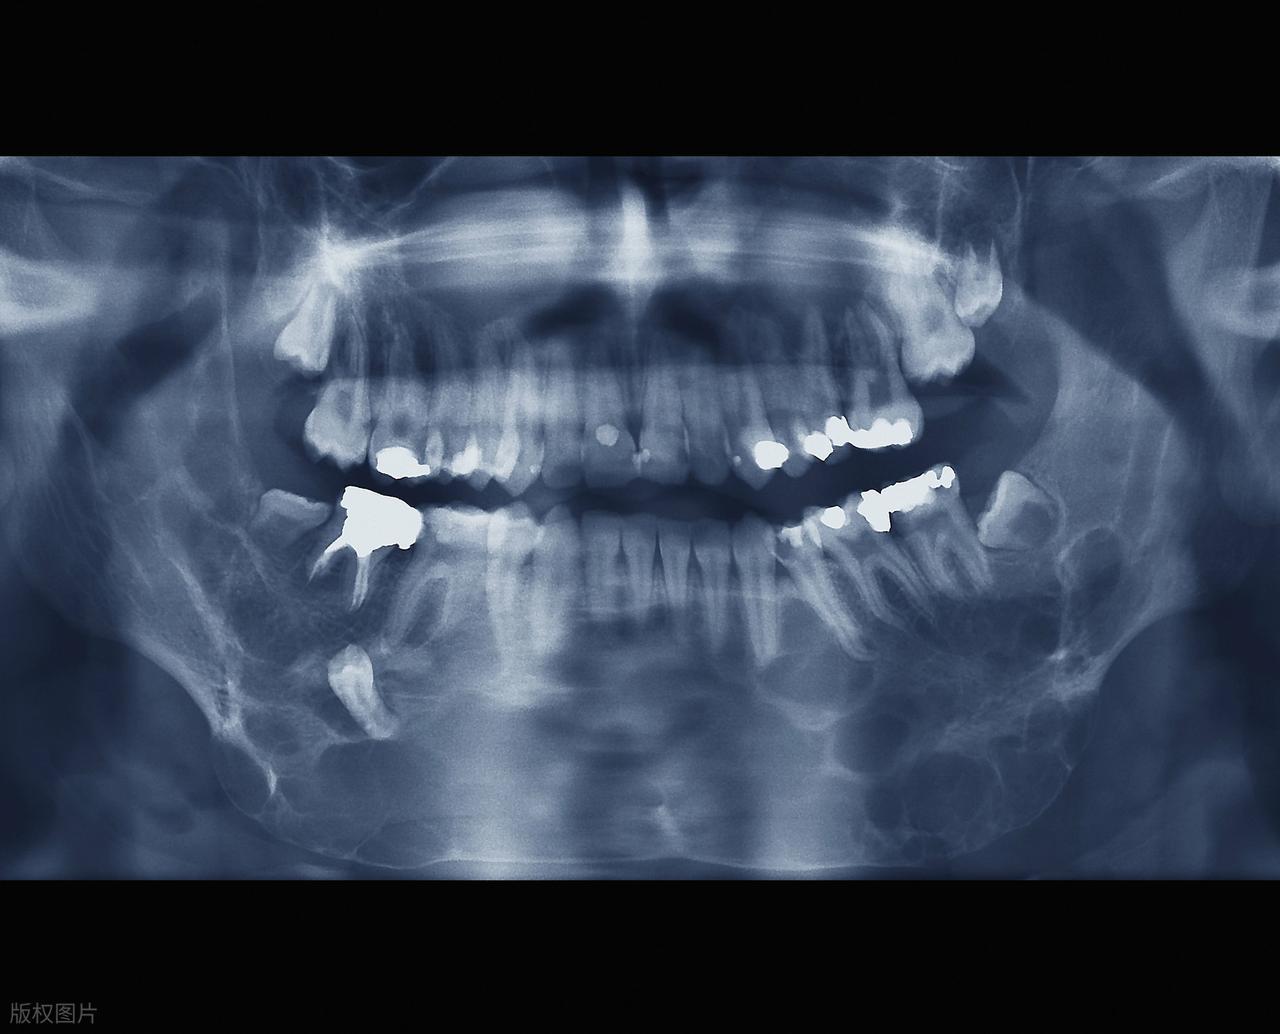

2.易出現阻生情況

由於頜骨空間不足,智齒很容易出現阻生現象,即智齒不能正常萌出或萌出位置不正。常見的阻生類型包括水平阻生、近中阻生、垂直阻生等。阻生的智齒可能只露出一部分牙冠,或者完全埋伏在牙齦下方,這不僅會導致萌出過程中的不適,還可能引發其他口腔問題。